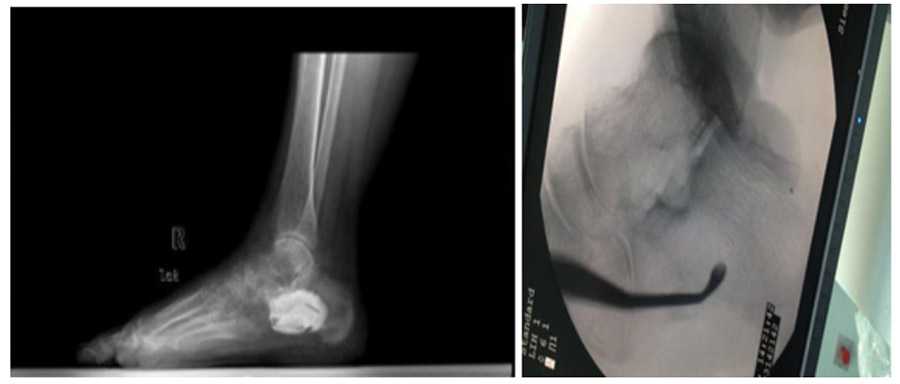

During and after surgery: The fluoroscopy shows the removal of the tumor with the help of a curette, and the filling of the resulting cavity with bone cement, as seen in the X-ray.